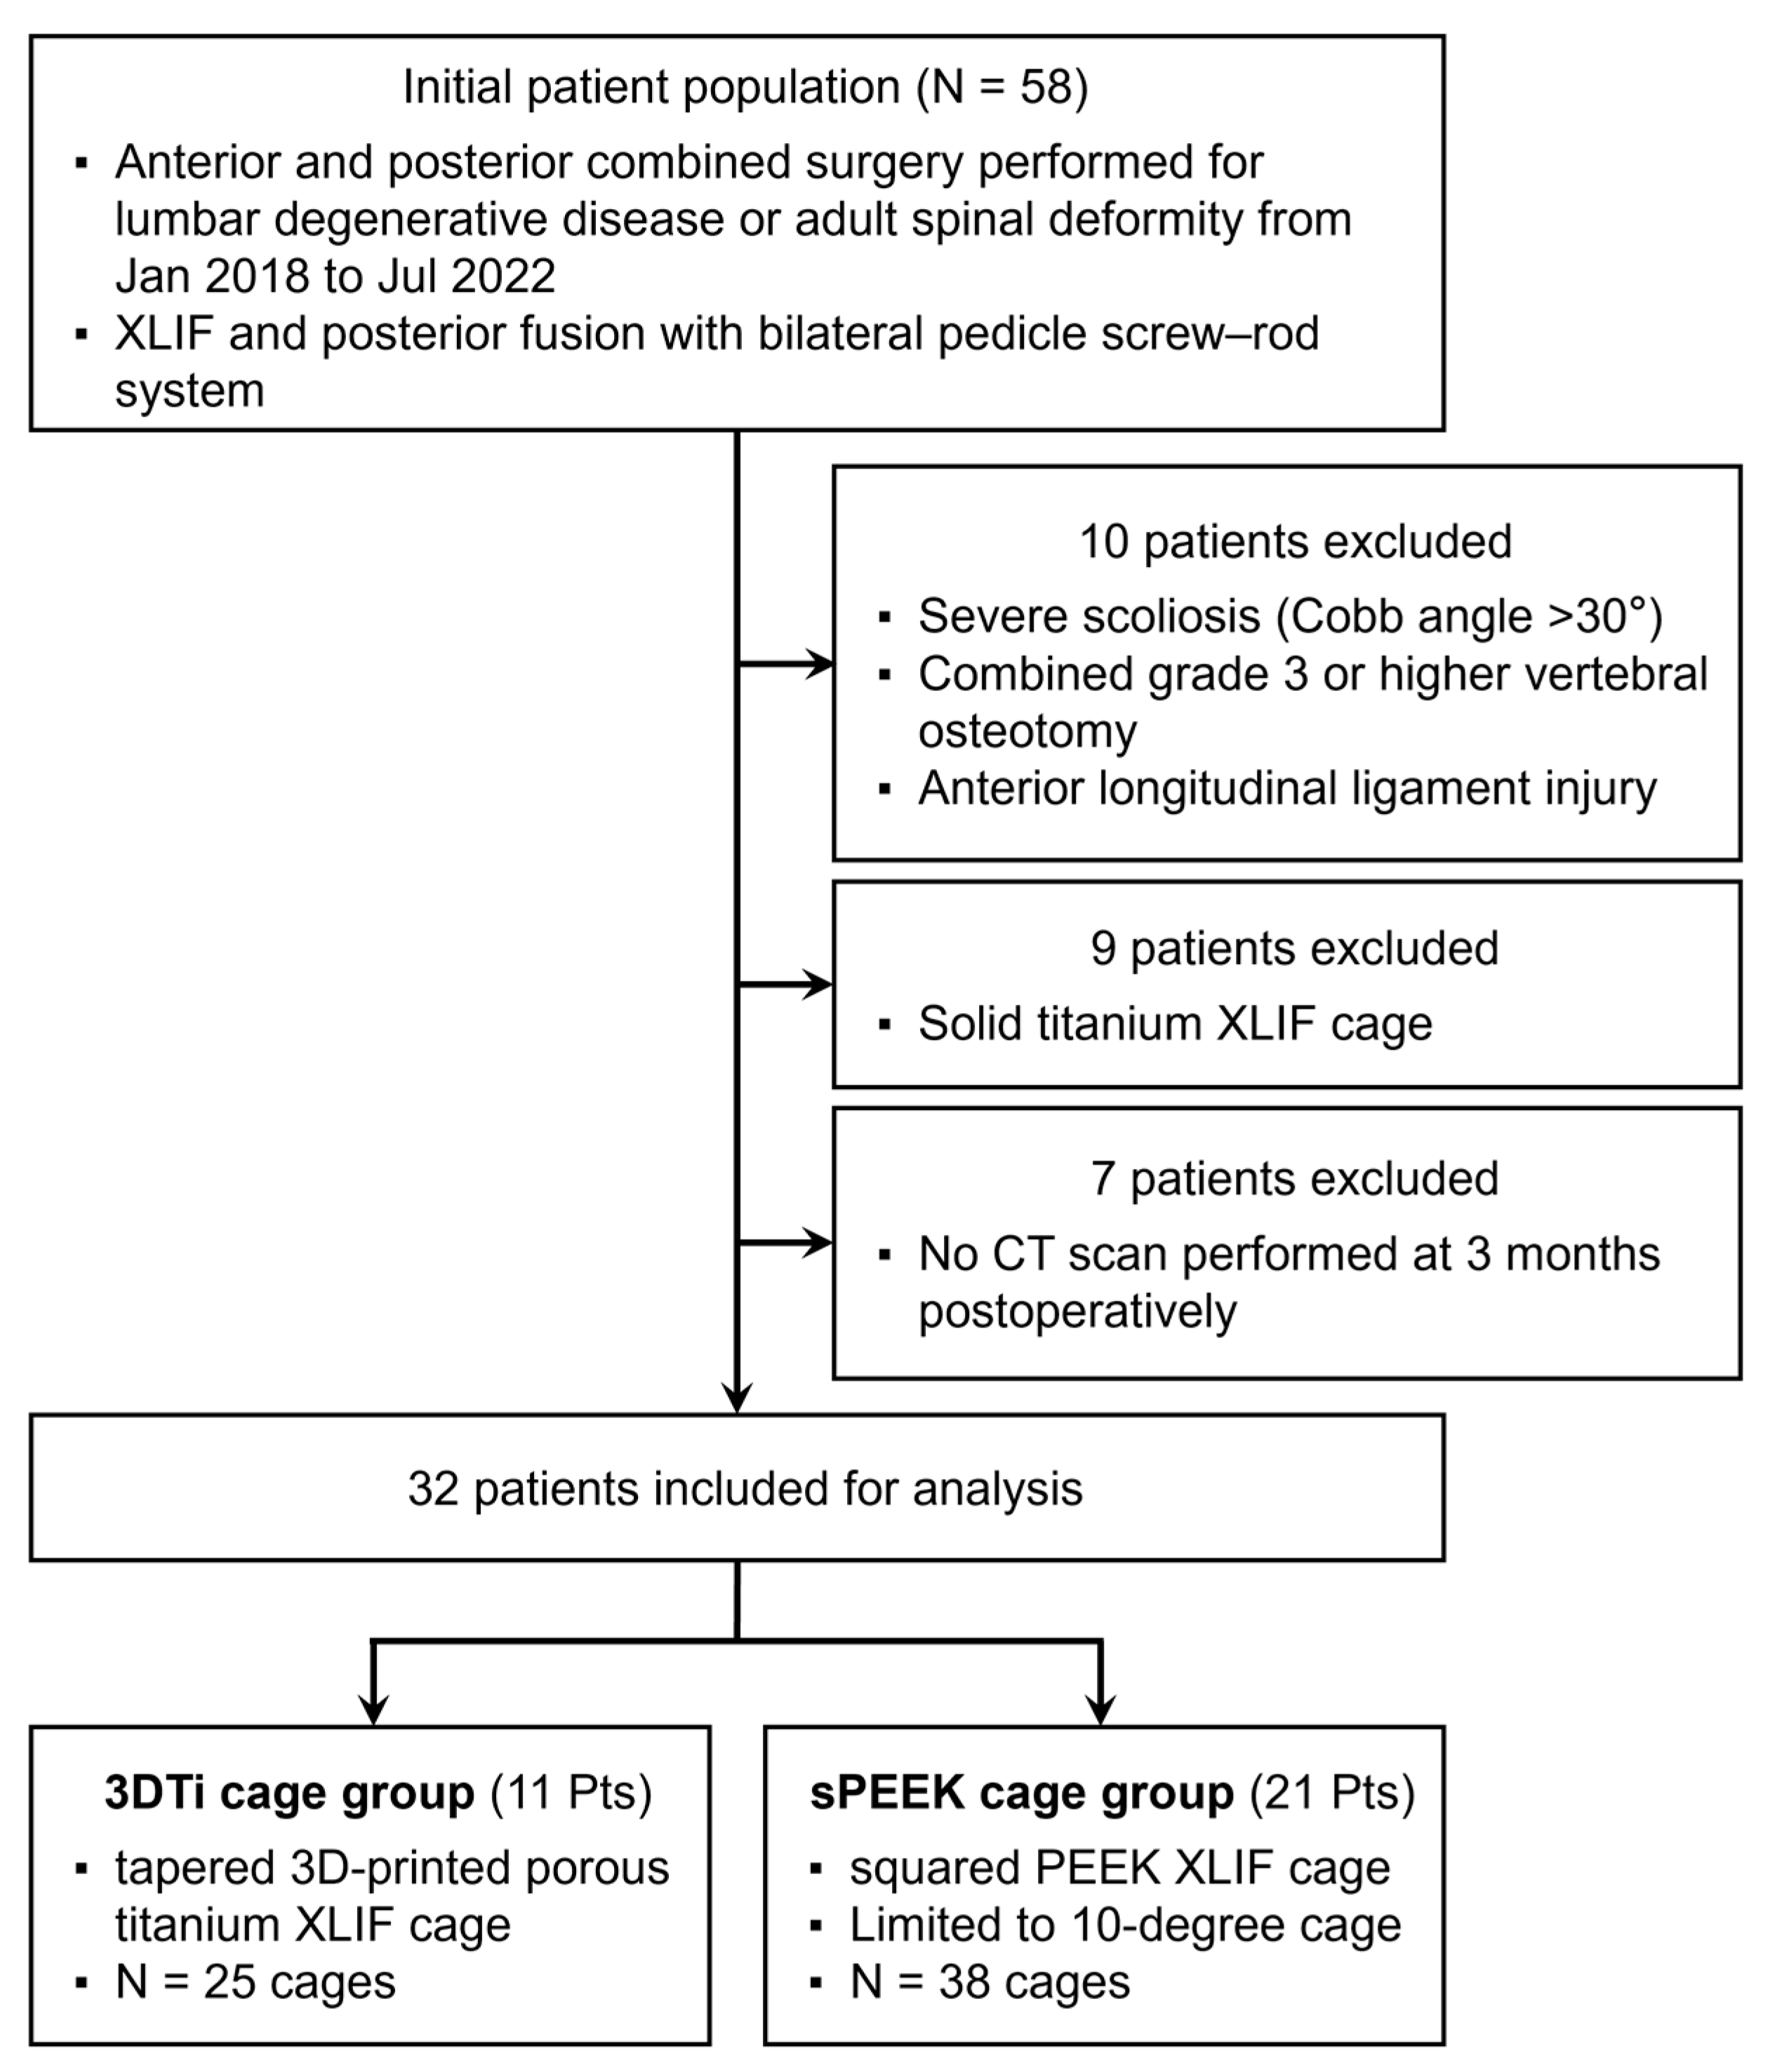

2. Materials and Methods

2.1. Patient Population